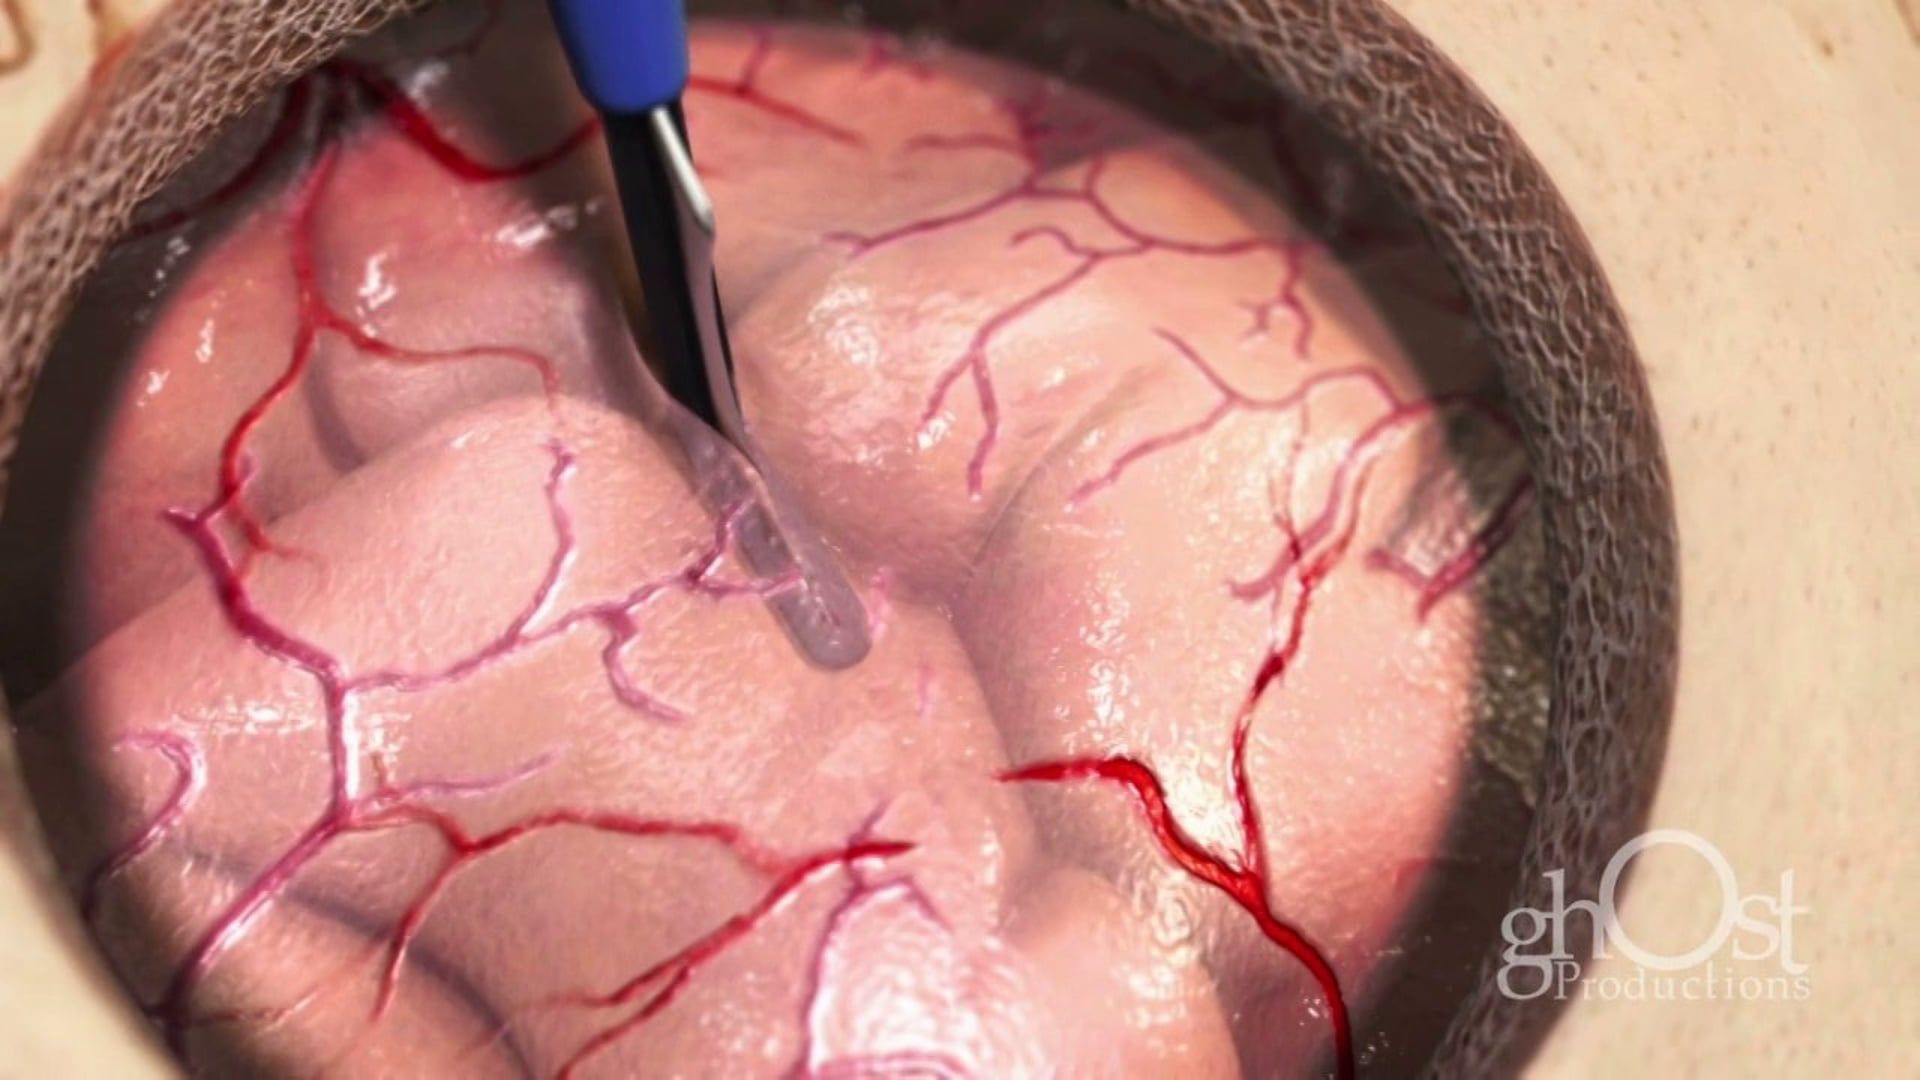

Medical Animation

Neurology